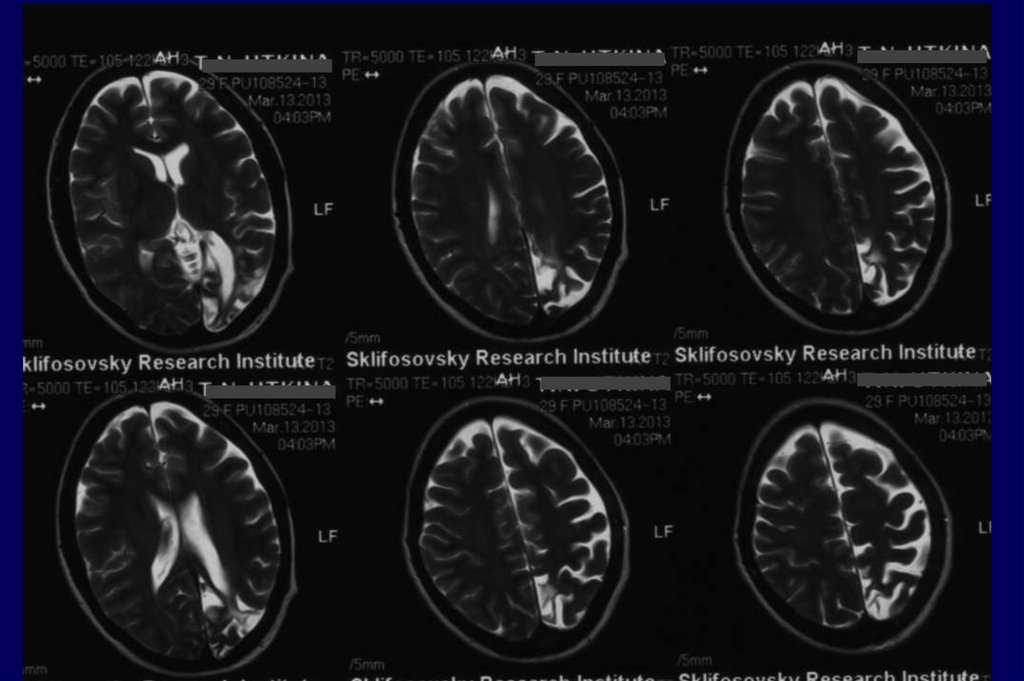

44. Аппаратные методы исследования:

• МРТ от 13.03.2013 – глиозно-кистозные

изменения преимущественно в левой

45. МРТ от 03.2013